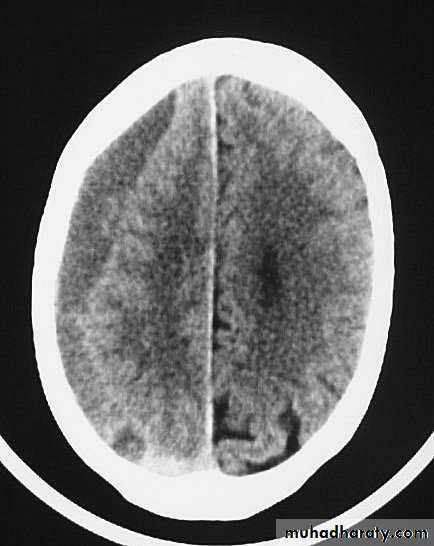

1. Diffuse Axonal Injury

Prolonged post-traumatic state in which there is loss of consciousness from the time of injury that continues beyond 6 hours.

Occurs as a result of mechanical shearing at the grey-white matter interface.

This causes disruption and tearing of axons, myelin sheaths and blood capillaries.

Severity can range from mild damage with confusion to coma and even death.